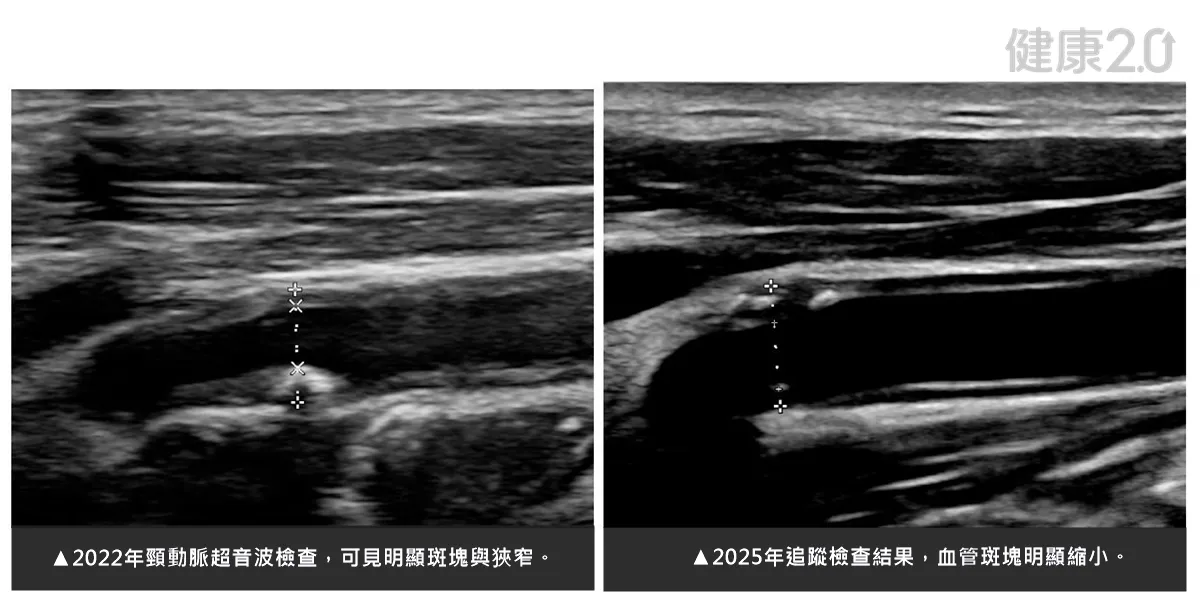

打從2018年起,這名癌友在心血管中心團隊照護下,每天規律服用斯他汀(Statin)類降血脂藥,並持續追蹤血管變化;在影像比對中,2022年雖然看到患者的頸動脈仍有明顯斑塊,但在持續使用高強度降血脂藥物之下,最新的2025年追蹤影像顯示,頸動脈斑塊體積明顯減少、血管壁恢復光滑,血流更為順暢,顯示治療獲得良好成效。

張恕桓醫師說明,斯他汀類降血脂藥除了降膽固醇外,也具有抗發炎與穩定血管的作用,有助於預防中風及心臟病發作。這位病人曾接受放射線治療,血管內皮容易受損,更容易形成粥樣硬化斑塊,在長期使用高強度降血脂藥物下,影像追蹤能觀察到明顯降低壞膽固醇(LDL)濃度,穩定甚至縮小斑塊體積。